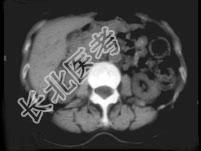

- 单项选择题男,74岁, 间歇性无痛性全程血尿2月余,尿路造影及CT平扫+增强如图所示, 下列说法错误的是 ( )

B、CT平扫示右侧肾盂内软组织块影